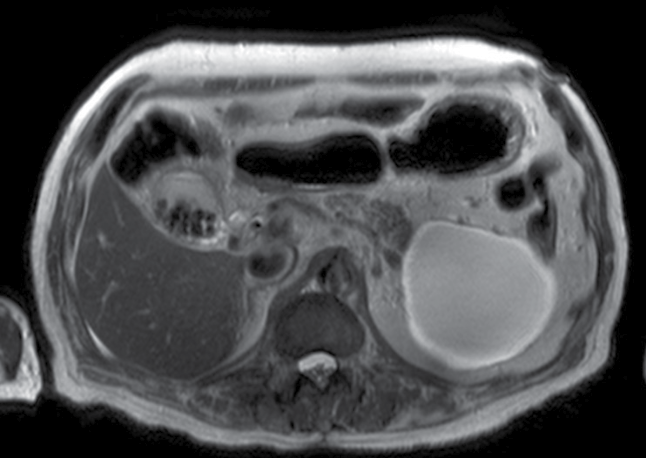

Paciente del sexo masculino de 87 años con dolor abdominal de 1 semana de evolución localizado en el mesogastrio, sin irradiación, escala visual analógica (EVA) 8/10; negó nausea, vomito o fiebre. Ingresó al servicio de urgencias, donde se solicitaron los estudios de imagen que se muestran en las figuras 1, 2 y 3.

4. ¿Cuál es el diagnóstico presuntivo con base en los hallazgos encontrados?